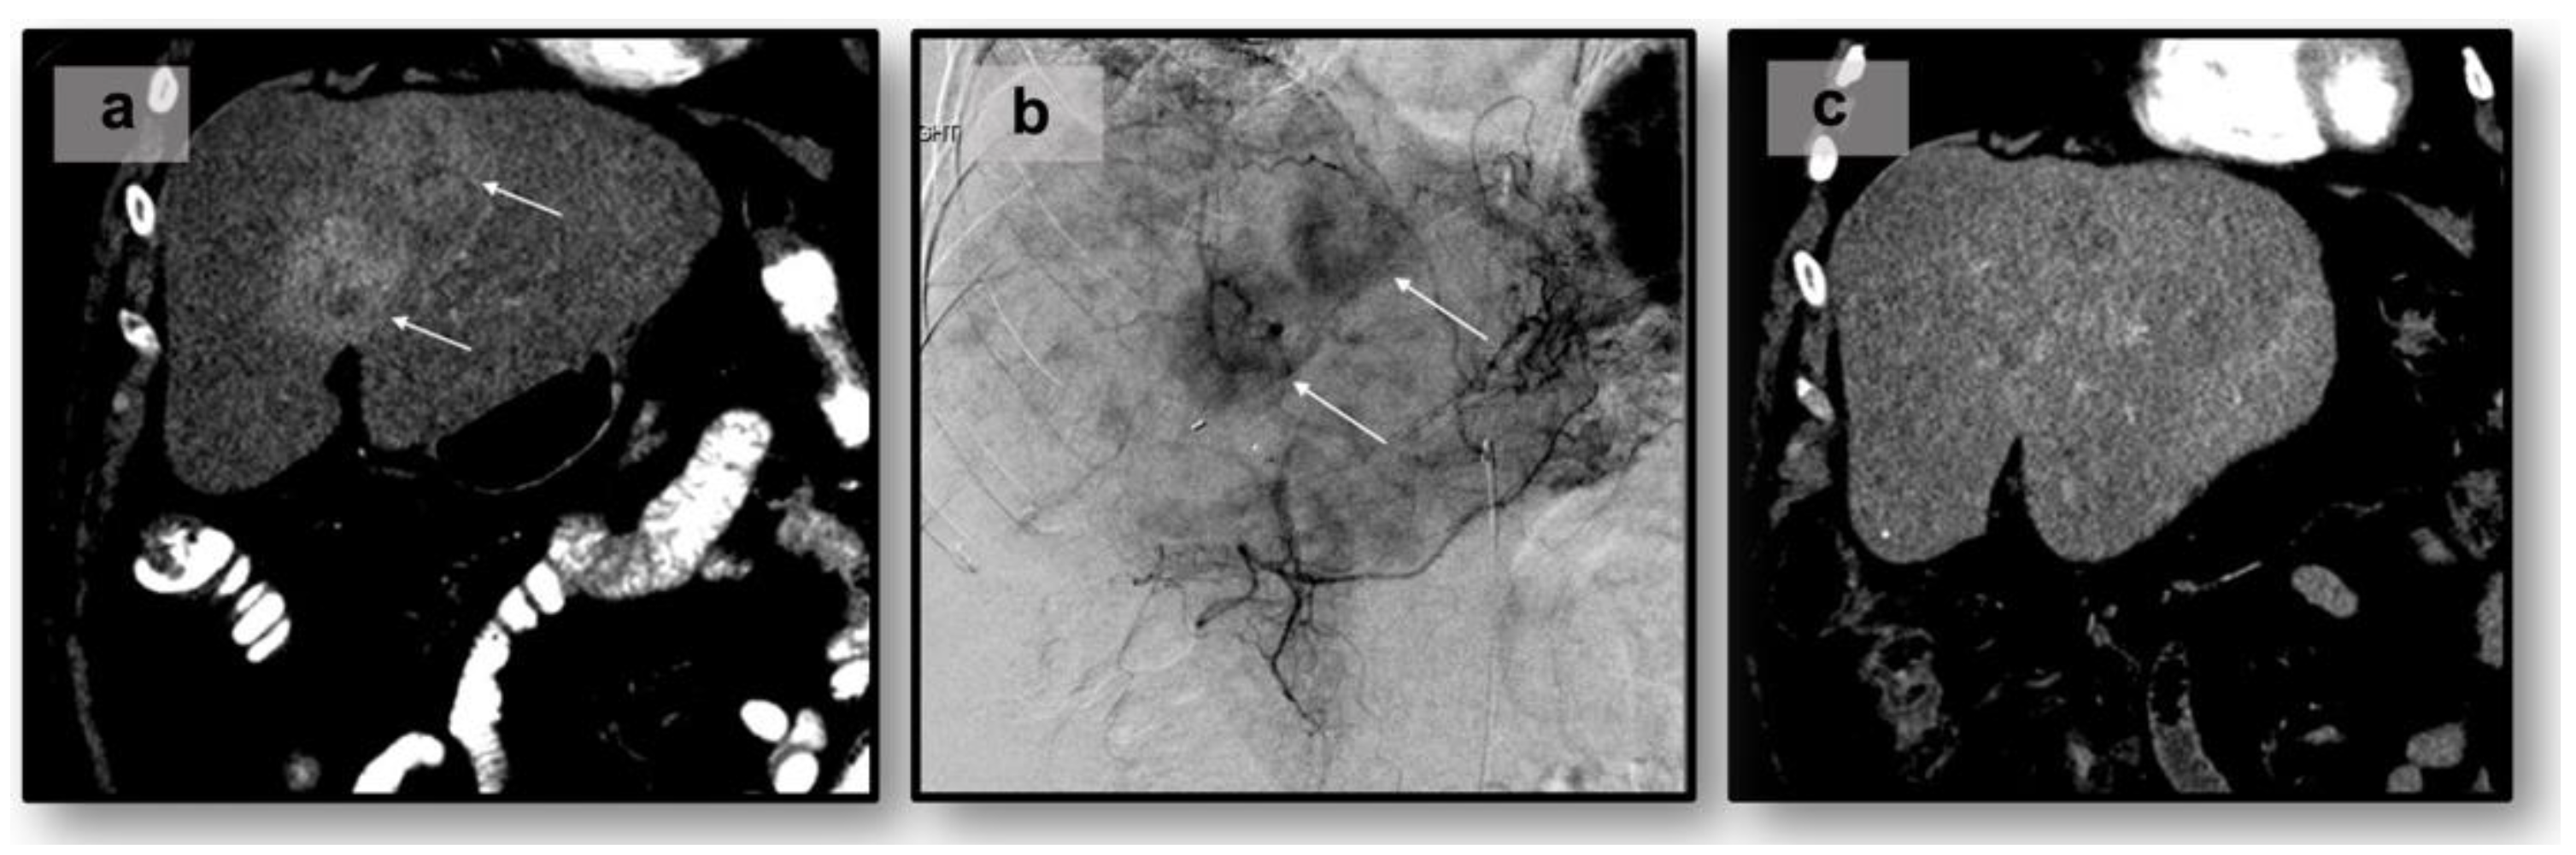

- Makary, M.S.; Kapke, J.; Yildiz, V.; Pan, X.; Dowell, J.D. Conventional versus Drug-Eluting Bead Transarterial Chemoembolization for Neuroendocrine Tumor Liver Metastases. J. Vasc. Interv. Radiol. 2016, 27, 1298–1304. [Google Scholar] [CrossRef]

- Makary, M.S.; Regalado, L.E.; Alexander, J.; Sukrithan, V.; Konda, B.; Cloyd, J.M. Clinical Outcomes of DEB-TACE in Hepatic Metastatic Neuroendocrine Tumors: A 5-Year Single-Institutional Experience. Acad. Radiol. 2023, 30 (Suppl. 1), S117–S123. [Google Scholar] [CrossRef] [PubMed]